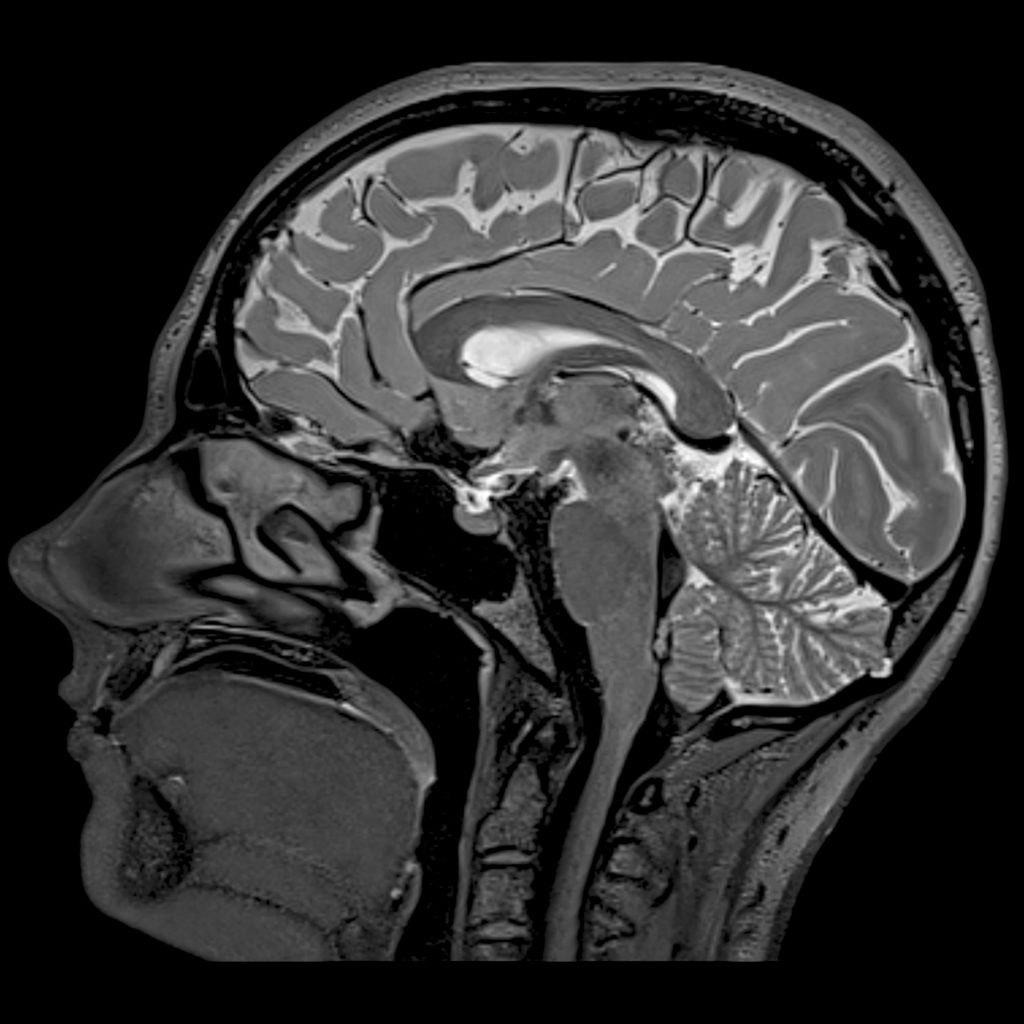

МРТ головного мозга: показания и результаты

Раздел: Визуальный дайджест